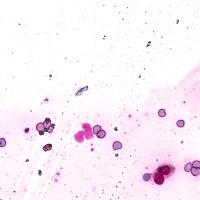

Medical Diagnosis: The "4class" model can be employed by pathologists to accurately identify and quantify the different cell types in blood and tissue samples, assisting in the diagnosis of various blood disorders and diseases, including anemia, leukemia, and infections.

Research and Drug Development: Researchers can use the "4class" model to analyze cellular response to experimental treatments, providing essential data for drug discovery, evaluating the efficacy of novel compounds, and understanding cell behavior under various conditions.

Education and Training: The "4class" computer vision model can serve as an educational tool for medical students and professionals, facilitating their understanding of different cell types, their characteristics, and functions, while promoting accurate identification in laboratory settings.

Automated Screening: Integration of the "4class" computer vision model into medical laboratory equipment can automate the process of cell classification during screenings or biopsies. This can help save time and reduce the risk of human errors during the evaluation of samples.

Telemedicine and Remote Analysis: The "4class" model can support telemedicine platforms, making it possible for healthcare professionals to remotely access and evaluate blood and tissue samples. This would be particularly useful in underserved areas, where access to pathologists might be limited.